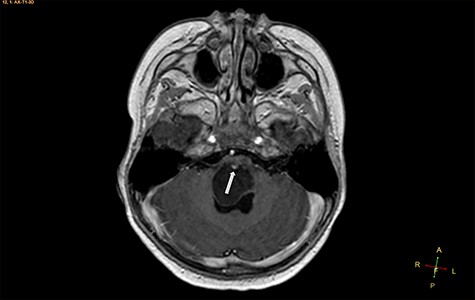

A 3-year-old male, who suffered from a sudden, tonic–clonic seizure, followed by a short period of unconsciousness, was instantly transported to Children’s Hospital 2. The patient’s medical history was normal. No neurological deficits were detected during the clinical assessment, and laboratory tests and electroencephalography were within acceptable ranges. The clinician performed a brain magnetic resonance imaging (MRI) scan, with contrast agent. No lesions were recognized in the supratentorial structures. A clear boundary cystic mass (27 × 25 × 26 mm3) was located in the medulla oblongata, without perilesional vasogenic edema. Hydrocephalus was not observed. The signal intensity of the mass was low on the sagittal T1-weighted image (Fig. 1) and high on the axial T2-weighted image (Fig. 2). On coronal fluid-attenuated inversion recovery imaging, the mass was isointense relative to the parenchyma, but the intensity was higher than that of cerebrospinal fluid (CSF, Fig. 3). On susceptibility-weighted imaging, no indicators of hemorrhage or ossification were observed within the mass. The mass was partially hyperintense on diffusion-weighted imaging (DWI) and slightly hypointense on the apparent diffusion coefficient (ADC) map. The mean ADC values of the parenchyma, mass and CSF were 0.71, 1.3 and 1.59 × 10−3 mm2/s, respectively (Fig. 4). On T1-weighted imaging, with contrast enhancement, the thin wall of the mass was very slightly enhanced, and we observed a tiny nodule inside the mass that was strongly enhanced (Fig. 5). With a provisional diagnosis of pilocytic astrocytoma, the patient underwent surgery to completely eradicate the tumor. Eventually, the histopathological result revealed a typical EC (Fig. 6). The postoperative period was uneventful, and the patient was discharged after 2 weeks.

Axial T2-weighted image, showing a hyperintense, cystic mass inside the medulla oblongata. Exceptionally, the lesion appears to progress from extra-axial to intraparenchymal (arrow).